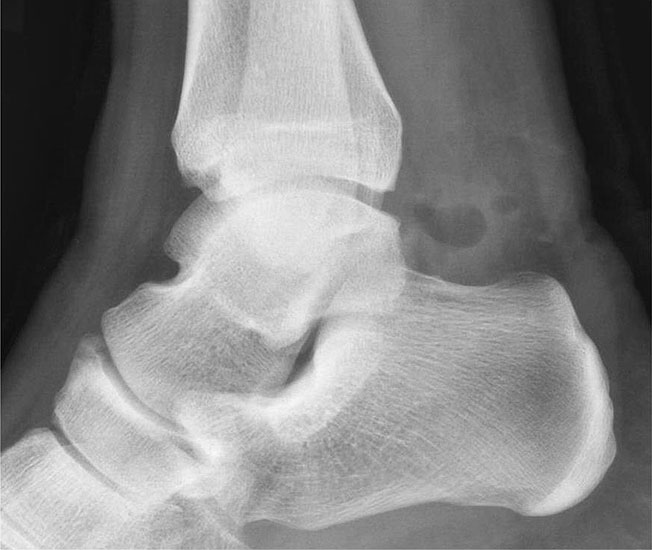

Abbildung Nr. 3 und 4

Die hohen paraachillären Zugänge befinden sich auf Höhe der Außenknöchelspitze unmittelbar medial und lateral der Achillessehne. Zur Identifikation der korrekten Zugangshöhe wird das OSG in Neutralstellung gebracht und eine Linie parallel zur Fußsohle gezogen, welche die Achillessehne kreuzt. Um den N. suralis nicht zu verletzen, wird die Haut nur vorsichtig inzidiert und die Weichteile mit einem Klemmchen aufgespreizt.

Abbildung Nr. 8-10

Es wird zunächst ein Weichteildebridement durchgeführt, bis die Flexor hallucis longus-Sehne identifiziert werden kann. Während des Debridements sollte auf die korrekte Ausrichtung der Instrumentenöffnung nach lateral geachtet werden. Im Verlauf empfiehlt sich der Wechsel auf eine bipolare Ablationselektrode, die eine gezielte Freilegung der Strukturen unter gleichzeitiger Blutstillung ermöglicht, ohne dabei unkontrolliert Gewebe anzusaugen (rechte Seite, m=medial, l=lateral). Das Os trigonum bzw. die Osteophyten sowie die FHL-Sehne müssen vollständig dargestellt werden (*=Os trigonum, FHL=Flexor hallucis longus-Sehne).

Abbildung Nr. 11-13

Das Os trigonum wird aus dem Weichteilgewebe gelöst und anschließend mit einer Fasszange entfernt. Bei größeren Knochenfragmenten muss ggf. das mediale Arthroskopieportal um wenige Millimeter verlängert werden, um die Extraktion zu ermöglichen. Nach Resektion des Os trigonum ist die posteriore Facette des Subtalargelenks erkennbar (rechte Seite, PF=posteriore Facette, FHL=Flexor hallucis longus-Sehne, T = Talus, K = Kalkaneus, *=Os trigonum).

Abbildung Nr. 14-16

Reseziertes Os trigonum sowie prä- und postoperatives seitliches Röntgenbild nach arthroskopischer Entfernung eines Os trigonum.